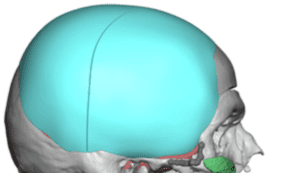

Desire for change of head shape from front view form an inverted V shape to a rounder and wider head shape.

Placement of custom extended forehead-temporal implants through incisions in the crease behind the ear. (he had a prior back of head skull implant which is green in the implant designs and which the head widening implants partially covered it)

Desire for change of head shape from front view form an inverted V shape to a rounder and wider head shape.

Placement of custom extended forehead-temporal implants through incisions in the crease behind the ear. (he had a prior back of head skull implant which is green in the implant designs and which the head widening implants partially covered it)